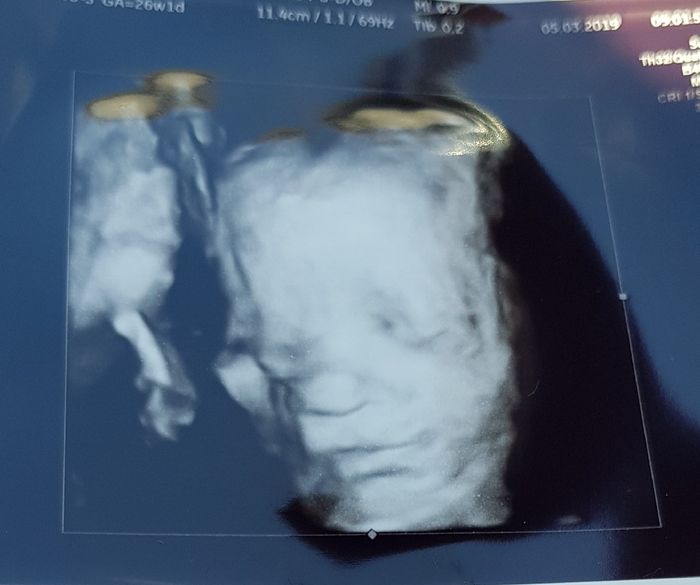

Ecco il mio super pancione che cresce...oramai siamo al sesto mese 😍 che meraviglia! ...e oggi abbiamo fatto i primi acquisti 😍